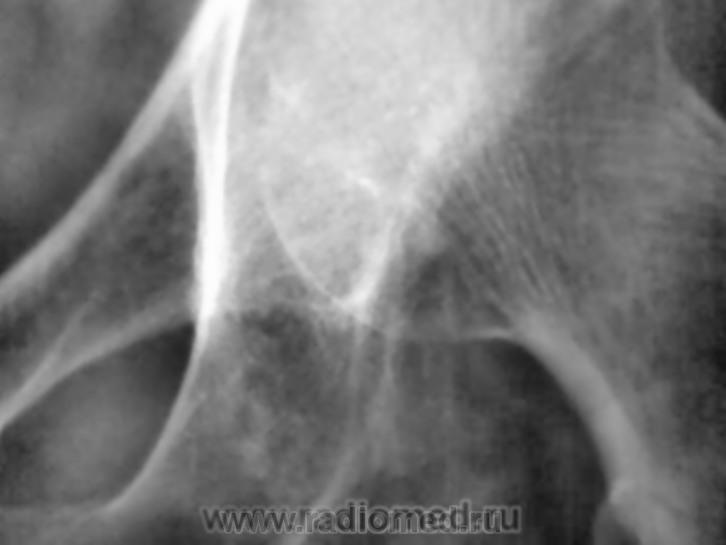

Неоднородность структуры седалищной кости за счет нечетких просветлений. В первую очередь, заподозрила бы мтс. На дополнительных изображениях вроде мягкотканный компонент по нижней границе суставной капсулы. Хотелось бы сравнительное изображение обоих суставов да и верхней/3 бедер

Не исключая остеолитический метастаз все же складывается мнение о суммации теней мягкотканного компонента, вот почему и было высказано мнение о пахово-мошоночной грыже.

Может пусть хирург пахово мошоночную грыжу поищет?.....

Остеолитический МТС?